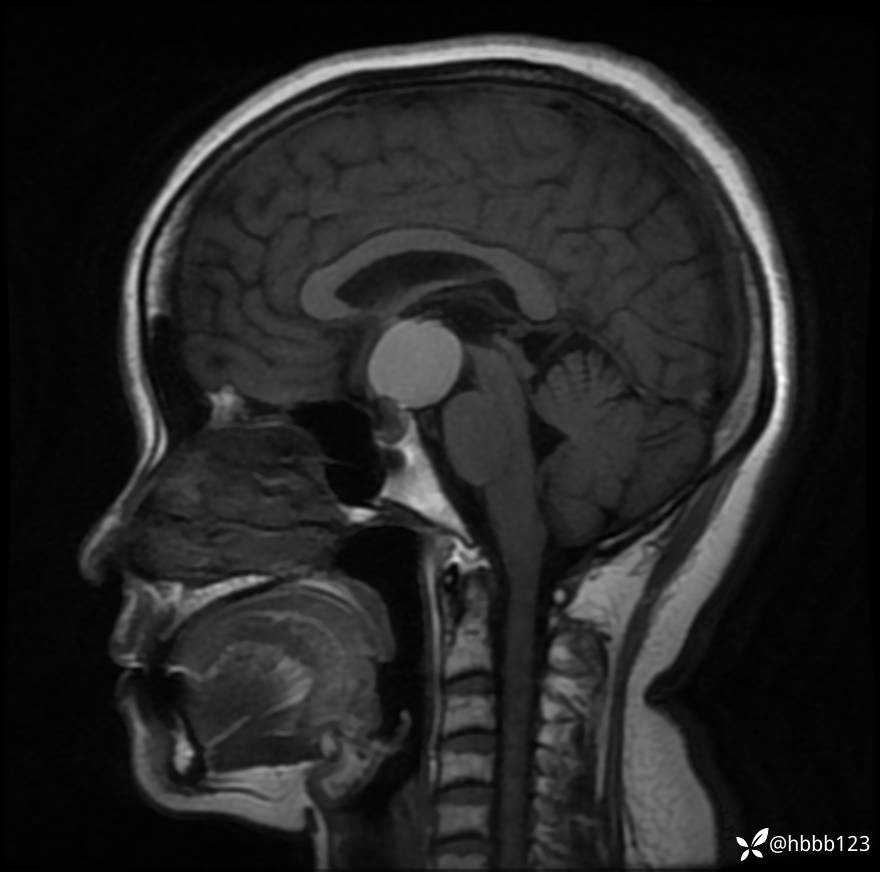

T1WI矢状位重建: